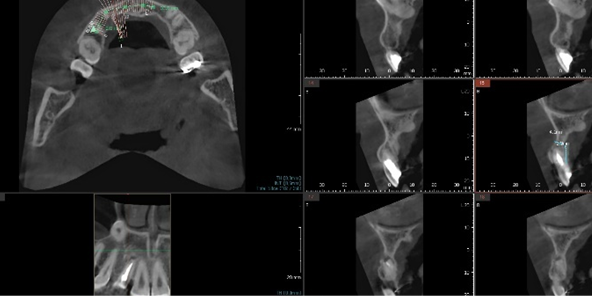

CT 정밀 분석 & 3차원 시뮬레이션

수술 당일을 위한 모든 준비를 수술 전에 미리 끝내는 단계입니다.

• CT 촬영을 통한 잇몸뼈·신경 위치 정밀 분석

CT 촬영을 통한

잇몸뼈·신경 위치 정밀 분석

• 3차원 분석을 통한 임플란트 식립 위치·각도·깊이 설정

3차원 분석을 통한

임플란트 식립 위치·각도·깊이 설정

• 개인별 수술용 가이드 제작

개인별 수술용 가이드 제작

• 임플란트 기둥 및 보철물 사전 제작

임플란트 기둥 및 보철물 사전 제작